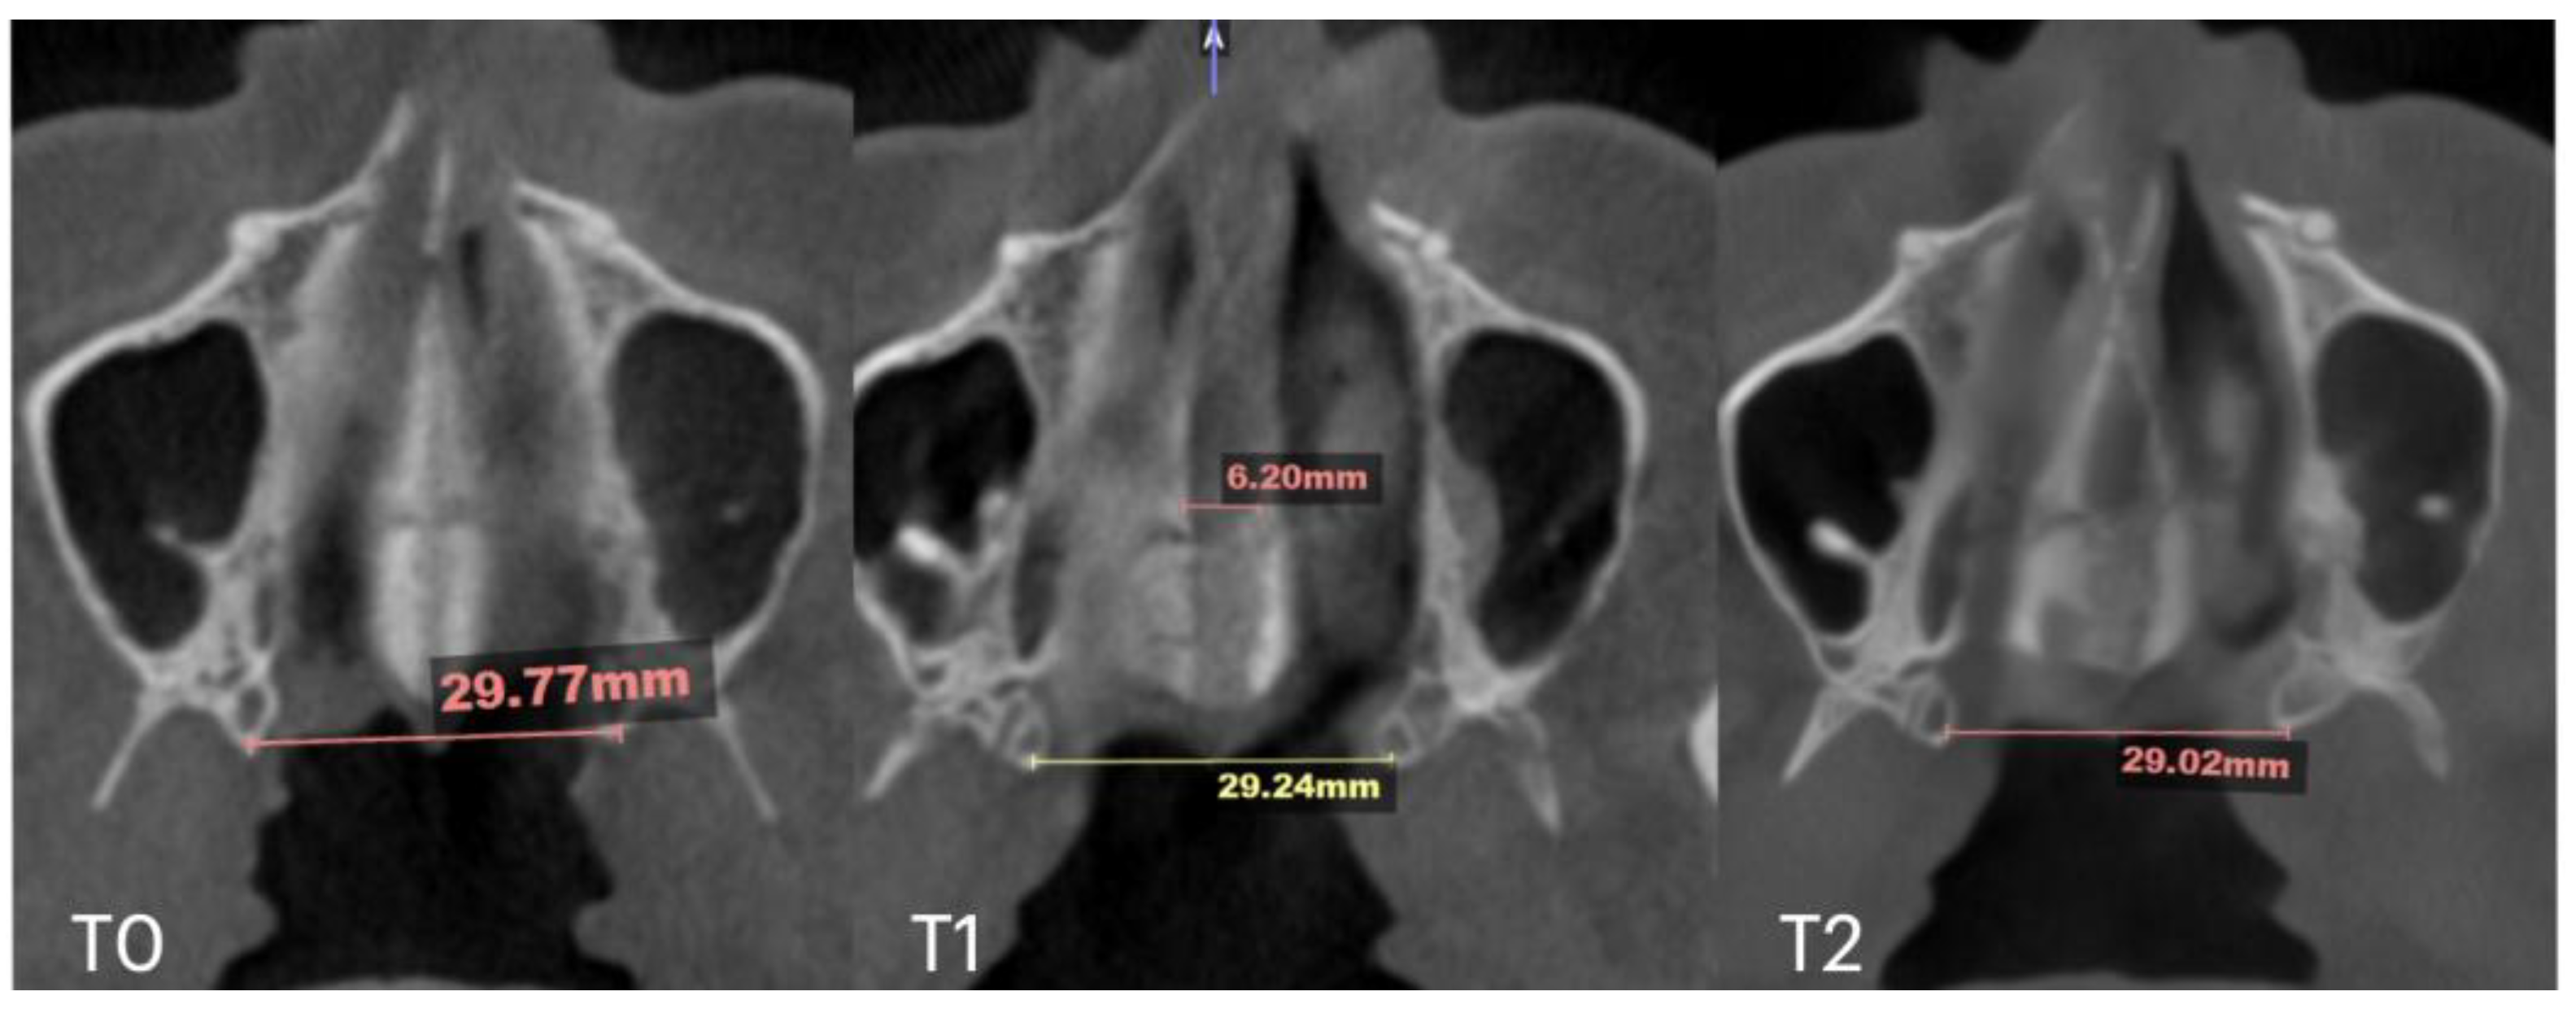

2.7. Case D: Midfacial Asymmetry Correction with Guided Expansion

| Case D | 26.25 | 33.27 | 31.54 | 55.9 | 61.84 | 60.37 | 33.98 | 35.94 | 38.09 | 29.77 | 29.24 | 29.02 | 6.2 |